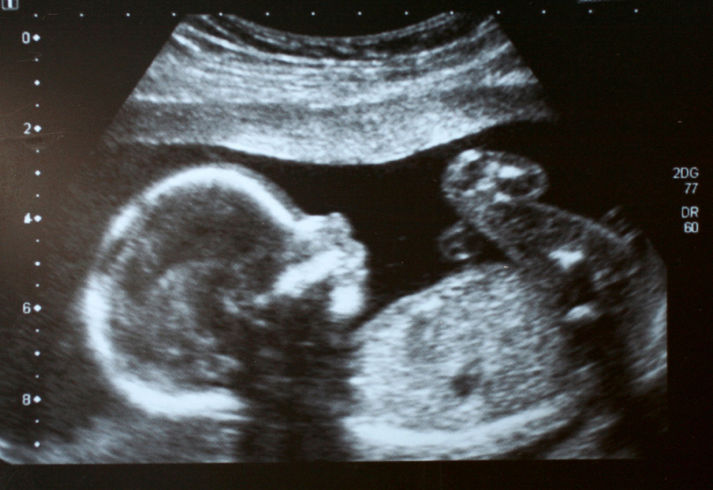

Sacha Rigby, una 22enne in dolce attesa, non poteva credere ai propri occhi. “Questo è il volto della mia bisnonna”, ha esclamato durante l’ecografia che ha svelato il sesso del nascituro.

Il volto dell’anziana, scomparsa lo scorso maggio a causa di una polmonite, è apparso accanto a quello del bambino ed è stato riconosciuto anche da Daniel, marito di Sacha. La coppia ha interpretato questa apparizione come un segnale positivo.